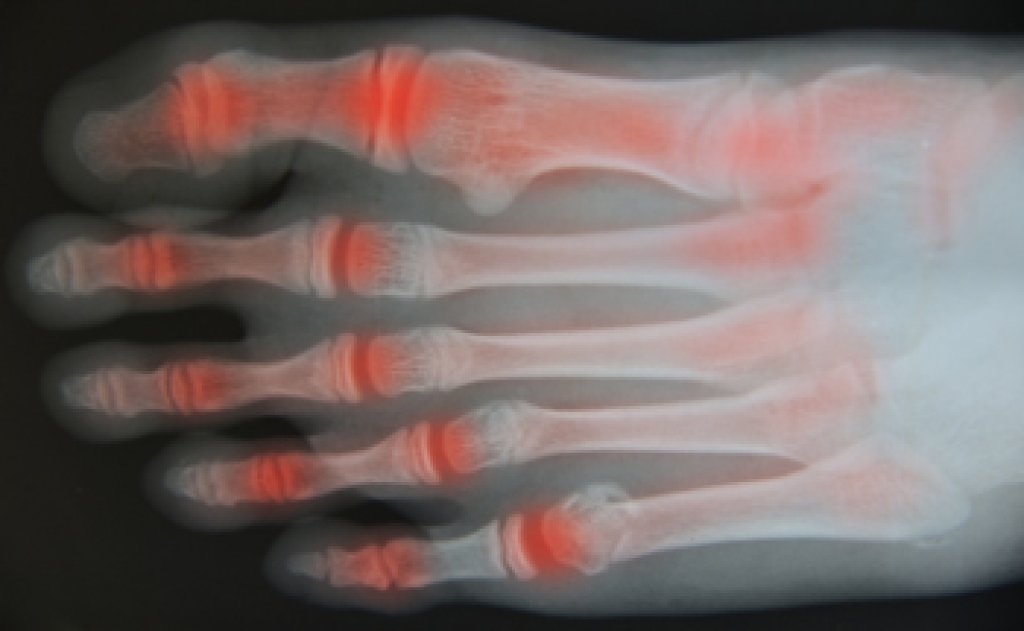

Diagnosis of cuboid syndrome is often difficult, and it is often misdiagnosed. X-rays, MRIs and CT scans often fail to properly show the cuboid subluxation. Although there isn’t a specific test used to diagnose cuboid syndrome, your podiatrist will usually check if pain is felt while pressing firmly on the cuboid bone of your foot.

Arthritis